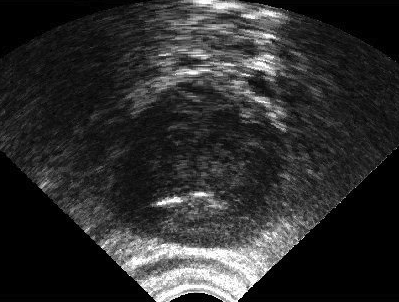

It is a challenge to validate any approach to segmentation. One has to measure the accuracy of the segment against ground-truth images. Ideally, if we have many users available to segment images, we can build “consensus segments”, or gold standard, to make more reliable measurements. Of course, this is usually not feasible with real images, for which there is no gold standard. Hence, we generated synthetic images whose gold segments were known a priori. For this reason, we used synthetic images that simulate transrectal ultrasound (TRUS).

TRUS images of prostates may be used to both diagnose and treat prostate diseases such as cancer. Starting with a set of prostate shapes , we created random segments through combinations of those priors, adding noise along with random translations and rotations, and we distorted the results with speckle noise and shadow patterns. Each image is thus created from its gold . Consequently, we can simulate user delineations by manipulating via scaling, rotation, and morphological changes, and we can simulate edits by running active contours with variable user-simulating parameters. The variability of user delineations was simulated according to several factors: error probability (), anatomical difficulty ( out of ), and the scaling factor for morphology (form to ). The user was modelled according to the level of experience (a random number from ), the user’s attention (a random number from ), and the user’s tendencies in terms of the segment size (a random number from ), whether tending to draw contours that are relatively small () or large ().

We generated 500 images from their corresponding gold-standard images111All images and their segments are available online: http://tizhoosh.uwaterloo.ca/. Furthermore, we generated 20 different segments for each image, assuming that there were 20 users. Figure 4 shows five examples of real and synthetic TRUS images. One should bear in mind that the purpose here was not to simulate the images realistically, but rather to have a base from which to generate variable segments from a perfect segment. Figure 5 shows an example of the gold segments and simulated user contours. The variability, coupled with the gold segment, is what is needed in our experiments.